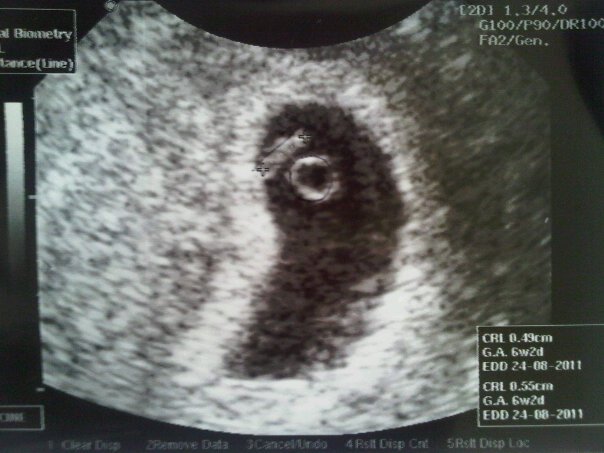

Teh Manda pendarahan. Untungnya dia lagi di Cimahi (di rumah orangtuanya) ngga di rumahnya, jadi langsung bisa dibawa ke rumah sakit. Habis di-USG, Alhamdulillah janin yang usianya 6 minggu itu baik-baik aja. Ngga kuat dibawa shaum sama tarawih kata dokter. Teh Manda disuruh ngga puasa 2 minggu. Tapi ga diturutin ama Teh Manda. Tetep shaum tapi tarawihnya di rumah biar lebih fleksibel, ga cape ngikutin imamnya. Teh Manda emang tipenya ngga kuatan kalo hamil katanya. Dari awal kehamilan udah dilarang momotoran lagi (ini saya ngomongnya berasa si teteh geng motor aja), terus pikirannya juga dijaga jangan stress terus. Si Aa langsung terbang dari Padang, nyampe tanggal 3 Agustus kemaren buat nengok sama nemenin teh Manda (nih ini baru balik).

| gini kira-kira janin usia 6 minggu |